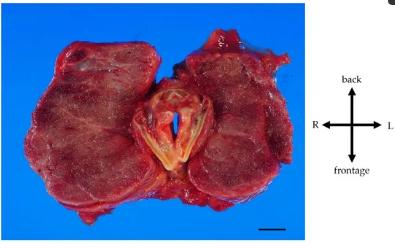

对其进行了病理解剖。甲状腺的大体检查结果包括弥漫性增大(重量675g,大小14cm× 6cm,正常重量20~30g,正常大小5cm× 2.5cm)和甲状腺对上气道的压迫性收缩(图4)。甲状腺的组织学发现显示甲状腺滤泡生长增加和胶质吸收增加,提示甲状腺机能亢进状态(图5)。

没有明显的恶性发现。关于其他大体发现,双侧主肺动脉扩张,肺重量增加(右1030 g,左1110 g,女性右肺正常重量200~500 g,左肺正常重量200~400 g)。右心室和心房也扩张了。观察到明显的右心肥大。这些发现提示慢性肺动脉高压。死亡原因被认为是由于持续静脉注射依前列醇治疗IPAH导致甲状腺肿大导致气道狭窄导致呼吸衰竭。

图4、甲状腺肿的大体检查结果